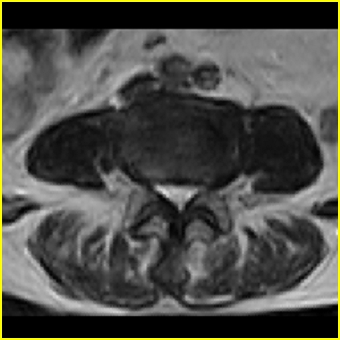

男,78岁,右下肢跛行两月.

右侧黄韧带肥厚或钙化,压迫马尾神经所致。必要时行ct扫描。

腰间盘膨出、黄韧带肥厚、可疑先天性腰椎管狭窄。

我认为这一层面椎间盘应该合并左外侧型突出。

退行性骨关节病:增生、椎间盘变性、膨出..黄韧带肥厚.

黄韧带肥厚.